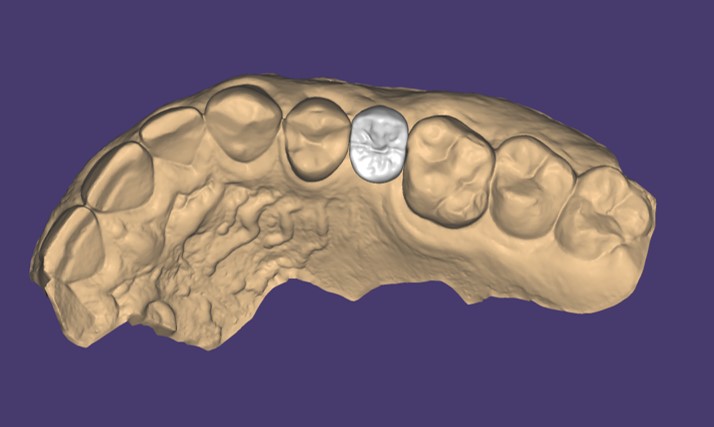

La scansione veniva inviata al laboratorio odontotecnico che procedeva alla modellazione, attraverso software di computer-assisted-design (CAD) (Galway®, Exocad, Darmstadt, Germania), di moncone personalizzato e corona definitiva (Fig. 11,12). La corona definitiva veniva stampata in 3D attraverso tecnica TSLA- titled stereolithography con stampante laser DFAB® (DWS Systems, Thiene, Vicenza, Italia) (Fig. 13).

Modellazione CAD di corona definitiva, visione occlusale

Fig. 11. Modellazione CAD di corona definitiva, visione occlusale.